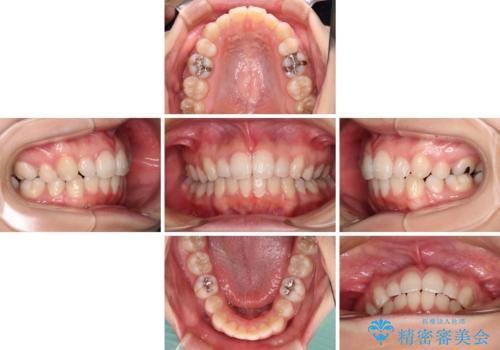

インビザライン・ライトで抜歯矯正の後戻りを解消

- 下顎前歯を中心に、以前行った矯正治療の後戻りが気になるとのことで来院された患者様です。

後戻りは軽度であったため、インビザライン・ライトにて治療を行うこととしました。

治療途中で出産をされたため、通院が困難となりましたが、インビザライン・ライトでの治療可能期限である2年以内に無事に治療を終えることができました。